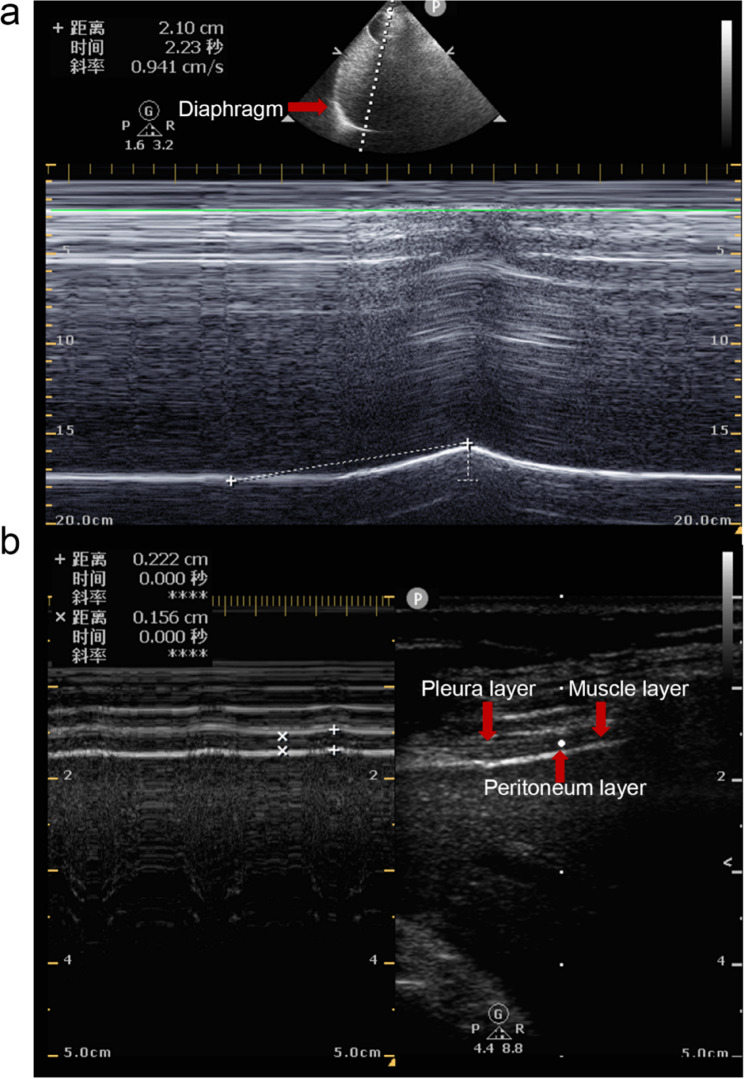

Methods: This cohort study included 110 patients who underwent elective surgeries under general anaesthesia. During recovery before extubation, diaphragmatic function was monitored via ultrasound with pressure support ventilation on continuous positive airway pressure (PS/CPAP). Concurrent respiratory parameters (tidal volume, respiratory rate, and PEEP) were also recorded. Patients were categorized into PARE and nonadverse respiratory event groups based on postextubation outcomes. A composite metric, MV×DE, was calculated by multiplying minute ventilation (MV) by diaphragmatic excursion (DE). Independent predictors of PAREs were identified using multivariate logistic regression, and the diagnostic accuracy of each indicator for PAREs was assessed using ROC curve analysis.